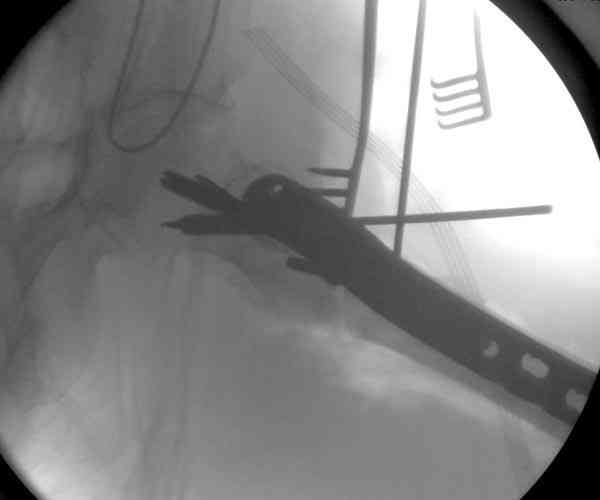

23.08.07г. на форуме был представлен больной 68 лет с диагнозом: несросшийся подвертельный косой перелом. http://www.weborto.net/forum/1187804790/ Больной после неудачной операции в одном районе в течении 7 месяцев был прикован к постели, с пролежнями в обл. крестца. Больной в течении 10 дней подготовлен к операции, НВ-153, эритр.-4,5, соэ-7, ВСК-3-3,40. ПТИ-81.ФНГ-3100. Мочевина, билирубин, АЛТ,АСТ в пределах нормы. Для остеосинтеза готовили пластину клинковую, штопор Сиваша . Во время операции дистальный отломок легко мобилизовали, проксимальный отломок был ротирован и сильно приведен медиально( m. iliopsoas), а также сильно замурован плотной как хрящ рубцовой тканью. Линия излома косая около 10 см., наружная стенка большого вертеля почти не было. У малого вертеля отсекли сухожилие m. iliopsoas и дальше на глубине начали распатором мобилизовать конец проксимального отломка, который был сильно приведен и находился глубоко , когда начали отделять изогнутом распатором заднюю часть конца и чуть подтянут отломка и тут начался сильнейшая кровотечения, фонтаном, найти сосуд и остановить кровотечение в ране не удалось, сосуд вместо с рубцовой тканью ушел назад и медиально отломка. Срочно рану туго тампонировали и остановили кровотечение, вызвали сосудистого хирурга,но их не нашли, оказалась один в отпуске, двое на экстренном вызове в районах. Передным доступом (по L. vasorum ) обнажали бедренную артерию, провели резиновую держальку и временно сосуд зажали, открыли рану , убрали тампон, но на глубине в толще рубцовых тканей поврежденный сосуд найти не удаётся. Поэтому переднюю рану расширили вниз, при ревизии бедренная артерия не повреждена, а глубокая бедренная артерия повреждена пристеночно, примерно на 2-3см от место отхождения от бедренной артерии, не доходя до ответвлений на огибаюших артерий. А одноимённая вена повреждена на протяжении около 3х см, и в данный момент восстановить не удается и пришлось перевязать оба конца, на артерию наложили поперечный сосудистый шов, бедренную артерию освободили, кровоток восстановился. Но теперь начала вся рана кровить! Венозный застой! К этому времени состояние больного резко ухудшилось, наступил клинический смерть, с трудом реанимировали, вроде б и кровотечение остановилось, как а/д подняли до 100/60мм опять начался кровотечение, коагулятором остановить не удаётся, рану туго тампонировали, перелито больше одного литра эр. массы и плазмы,и ешё кровозаменители, стабизол, рефортан и др. а/д держим 90/60, интесивная терапия против ДВС синдрома. Реаниматологи не разрешают производить остеосинтез, так как гемодинамика нестабильная , держиться под вазопрессорами. Через час состояние больного не улучшается , реаниматологи дали 10 минут и мы быстро кое как репонировали, остеосинтез продолной пластиной ЦИТО, но шурупы в проксимальном отломке плохо держутся, (остеопороз ), но другого выхода не было, для клинковой пластини просто небыло времени. Тканевое и капиллярное кровотечение продолжается, рану туго тампонировали и наводяшие швы на рану. Наложили гипсовой сапожок с деротатором. Больной находился в общей реанимационной отд. 20 дней и вышел из критического состояния. Но на контр. Р-грамме шурупы как и предпологали не держались, имеется ротация проксимального отломка, хотя ось бедра правильная и клинически деформации нет, даже определяется клиническая схватка . Я долго думал, вынести это на форум или нет, позвонил Челнокову А Н, он сказал <надо быть честным до конца, доложил на форуме, надо сообшить и о резултатах> Уважаемые коллеги! Какие были допушены ошибки? И какие рекомендации будут теперь? . P. S. за некачественный р-снимок прошу прошения!

Адекватная фиксация достигается длинным 95 градусным Blade Plate, где клинок пластины, связывая головку со средней трети бедра, создал бы условия для сращения.

Другой вариант пластины, это Synthes Proximal Locking Plate предназначенный для лечения прксимальных переломов бедра, где три шурупа: два 7.3 мм, введенных в головку под углом 95, 120 и 5.0 мм в 130 градусов, создают угловую стабильность.

Ровно эту же самую роль мог бы сыграть и штифт - гамма или другой проксимальный. Мы бы, скорее всего, планировали в таком случае гамму. И вместо проведенной операции, и сейчас, если все-таки будет несращение. Возможно, после непрдолжительной коррекции положения отломокв в аппарате.